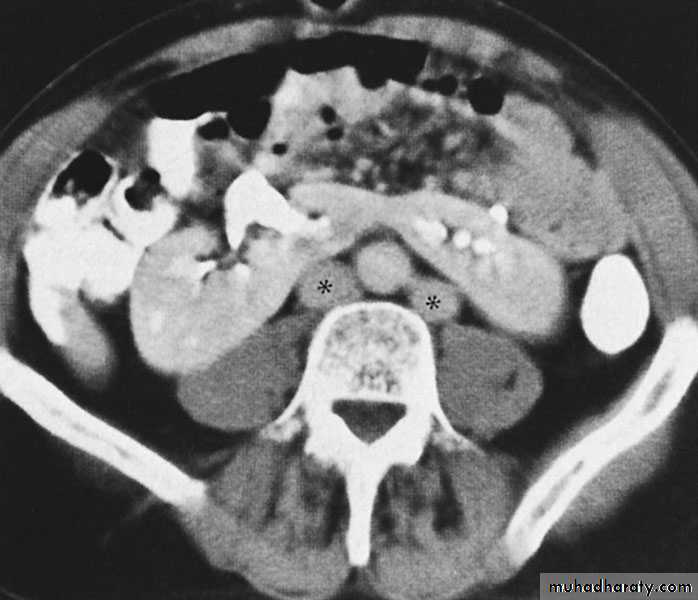

Horseshoe Kidney

found in 1:1000 necropsies an is commoner in men.

probably the most common of all renal fusion anomalies

The anomaly consists of two distinct renal masses lying

vertically on either side of the midline and connected at

their respective lower poles by a parenchymatous or fibrous

isthmus that crosses the midplane of the body.

Fusion of the renal masses early in embryonic life, so its ascent

will be impeded by inferior mesenteric artery.

The kidneys are low located, mal rotated and pelves lie anteriorly

Symptom When present, they are related to complications like hydronephrosis, infection, or calculus formation

Diagnosis ultrasound, IVU, CT scan

Treatment:

-Medical: pain relief and to control infection

-Surgical: stone removal, PUJ stenosis correction and isthmus division in cases of

-operations on the aorta

Prognosis usually they have normal life.